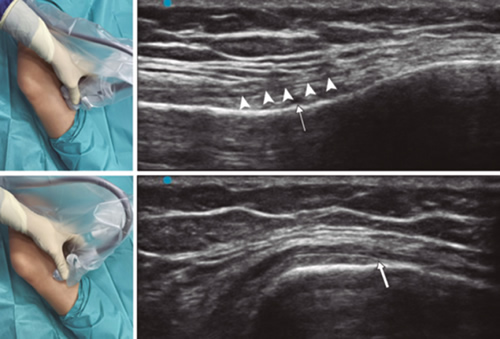

Radiofrecuencia de los nervios geniculados guiados por ecografía

Para lograr una correcta ubicación de las referencias anatómicas por ultrasonido debemos colocar al paciente en posición supina con la rodilla flexionada y una almohada debajo de la fosa poplítea (14,16,19). Después de realizar asepsia/antisepsia de la rodilla, colocación de campos quirúrgicos y de la funda estéril del transductor lineal de alta frecuencia, procedemos a ubicar el NGSM (Figura 3). Colocando la sonda en un plano coronal sobre la cara interna de la rodilla, la deslizamos en sentido craneal hasta visualizar la unión de la metáfisis con la diáfisis femoral y la arteria/nervio geniculado superomedial (ANGSM), usualmente están localizados cerca al periostio del fémur (en caso de no encontrar esta estructura neurovascular, se toma como referencia la unión de la metáfisis y la diáfisis femoral). Después se marca en la piel el punto medio del transductor que corresponde a la ANGSM y se gira el transductor para ubicarlo en el plano transversal o axial para visualizar la ANGSM en eje corto (si no es posible la visualización de esta estructura, confirmar que estamos a un 50 % de la profundidad del fémur). En este corte transversal se avanza la aguja de RFT en plano desde anterior a posterior hacia la ANGSM o hasta una profundidad del 50 % del espesor del fémur. Finalmente se vuelve a girar el transductor 90°, dejándolo en un plano coronal para comprobar que la punta de la aguja está cerca de la ANGSM o de la unión de la metáfisis y la diáfisis femoral (14,16,19).

Fig. 3. Sonoanatomía y técnica para realizar el bloqueo del nervio geniculado superomedial (NGSM). El transductor se ubica en el eje largo distal del fémur y una vez que se tenga la posición del NGSM (asteriscos), se gira la sonda 90 grados para obtener una visión en eje corto del fémur (no olvidar mantener la misma profundidad a la que encontramos el NGSM en el eje largo). VM: vasto medial.

Para ubicar al NGIM (Figura 4) colocamos el transductor en un plano coronal sobre la cara interna de la rodilla, lo deslizamos en sentido caudal hasta identificar la unión de diáfisis con la metáfisis tibial y la arteria/nervio geniculado inferomedial (ANGIM), y repetimos los mismos pasos que usamos para el NGSM. En caso de no encontrar la ANGIM, la referencia que se tomará será la profundidad del 50 % del espesor de la tibia (14,16,19).

Fig. 4. Sonoanatomía y técnica para realizar el bloqueo del nervio geniculado inferomedial (NGIM). El transductor se ubica en el eje largo proximal de la tibia e identificamos el paquete vasculonervioso del NGIM (flecha) justo debajo ligamento colateral medial (puntas de flechas). Luego se gira la sonda 90 grados para obtener una visión en eje corto de la tibia (no olvidar mantener la misma profundidad a la que encontramos el NGIM en el eje largo).

Para ubicar el NGSL, el paciente debe estar en posición supina con el miembro inferior en rotación interna, consiguiendo una buena exposición de la cara lateral del muslo. Colocamos el transductor lineal en un plano coronal sobre la cara lateral de la rodilla, lo deslizamos en sentido craneal hasta visualizar la unión de la metáfisis con la diáfisis femoral y la arteria/nervio geniculado superolateral (ANGSL), y repetiremos los mismos pasos que usamos para el NGSM (14,16,19).

Después comprobamos que el umbral de estímulo sensitivo a 50 Hz que desencadene una parestesia o dolor sea menor de 0,6 V, y para evitar daño de nervios motores no debe existir fasciculaciones del miembro inferior con un estímulo motor a 2 Hz con 2,0 V. Si todo está correcto, administramos 2 ml de lidocaína al 2 % o mepivacaína al 2 % en cada nervio y procedemos a realizar la RFT a 80 °C durante 90 segundos (9,14).

En nuestra revisión encontramos otras referencias anatómicas que nos pueden ayudar a localizar los nervios geniculados. Yasar y cols. (20) identificaron que el NGSM se localiza un centímetro anterior al tubérculo aductor, el NGIM se localiza en el punto medio entre el pico del epicóndilo tibial medial y el inicio de la inserción de las fibras del ligamento colateral medial sobre la tibia.